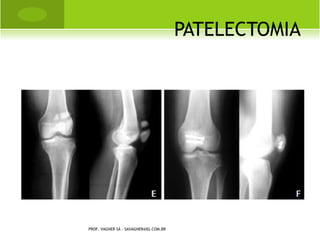

P SEUDO - ARTROSE PATELA

PATELECTOMIA